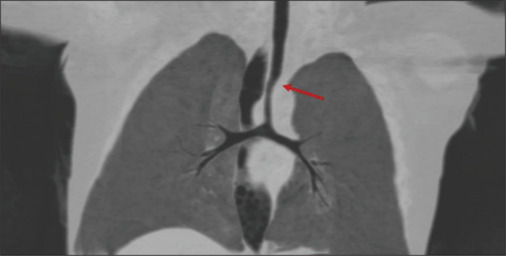

Imaging of a baby with recurrent airway infections.

Stridor, choking episodes and recurrent respiratory infections are common causes of referral for echocardiographic evaluation of the cardiovascular system. Vascular anomalies are rare but important causes of airway symptoms and/or feeding difficulty in young infants and should be carefully evaluated during echocardiogram.